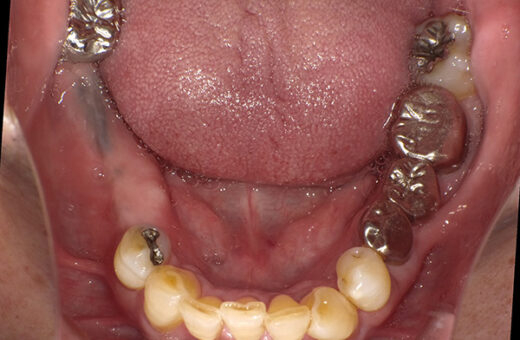

インプラント 70代(男性)

治療前

主訴

右下の義歯が合わない

症例詳細